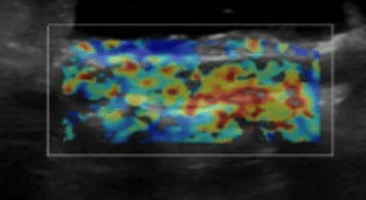

Magnetic resonance imaging has proven to be very valuable in the assessment of pathology within the spine (Weiner and Patel, 2008). MRI uses the body’s natural magnetic properties to produce detailed images. It can be used for all parts of the body, but in veterinary medicine we mostly use it to obtain images of the brain and spinal cord. There are no known biological hazards of using MRI as it uses radiation from the radiofrequency range which is found all around us, causing no harm to tissues. This differs from radiography and computed tomography (CT). It is important to check whether patients needing an MRI have any pacemakers, metal clips or metal valves as these will pull towards the magnetic field, which can be dangerous. Metal joint prostheses or implants, however, can be put through the MRI scanner, but these usually cause artefacts on the image (Berger, 2002). MRI will allow you to identify whether there is any pathology in the spinal cord and gives very detailed images showing how much the spinal cord is being compressed and at what location (Figure 1).

MRI is the most accurate and beneficial form of diagnostic imaging to identify a spinal lesion, whether this be a disc extrusion, ANNPE, tumour or FCE. Timing is very important with neurology patients; if the patient is nociception-positive on arrival at the hospital, they have a much better chance of a full recovery. Seeing these patients as soon as possible after a trauma or clinical signs occur is key.